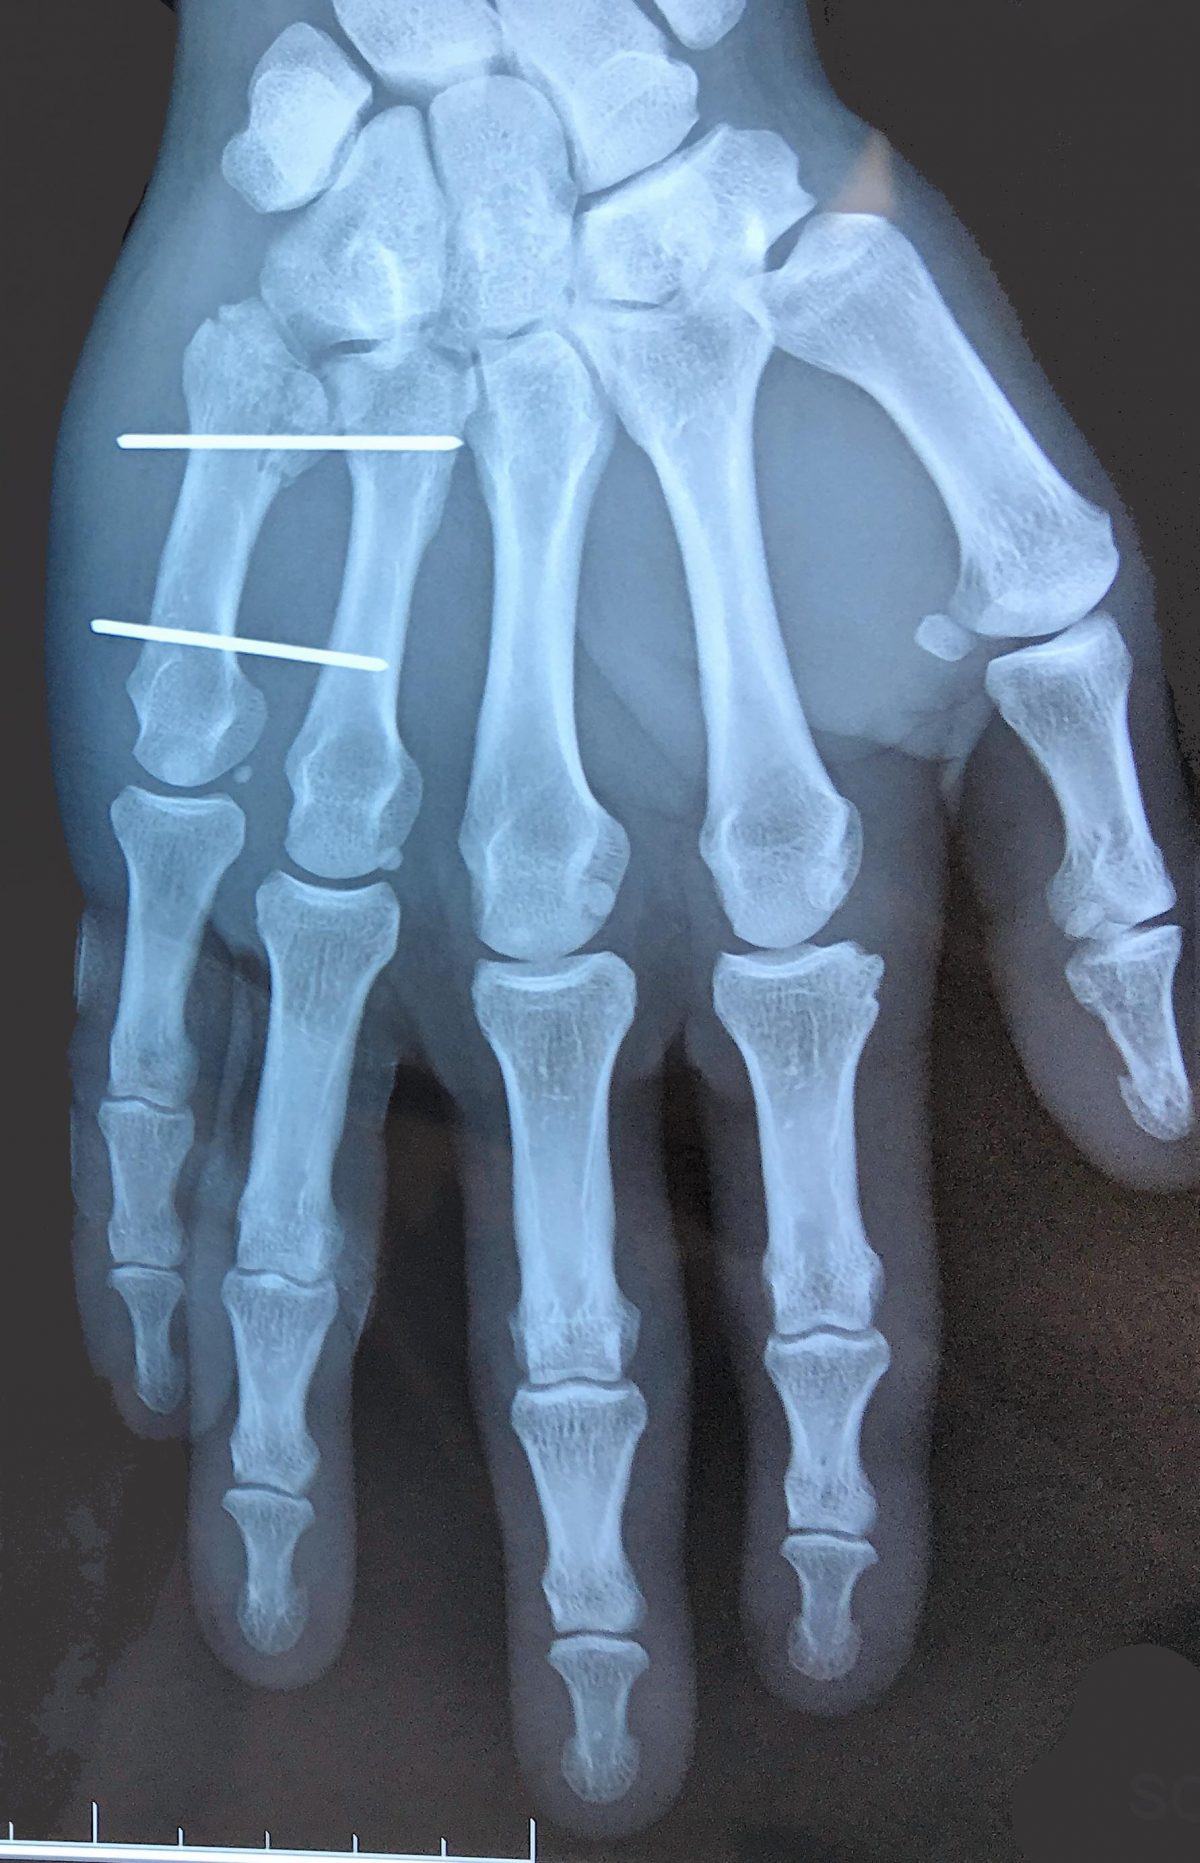

Broche Fracture Metacarpe Photo. Fractures de la main Pathologies Institut Européen de la Main Diagnosis is made by orthogonal radiographs the hand Fracture de la tête, de la diaphyse et de la base du 5e métacarpien Les fractures du 5e métacarpien sont fréquentes

Fractures de la main L'institut de chirurgie de la main de l'ouest parisien. Scaphoide : fracture et pseudarthrose; Maladie de Kienbock; Chirurgie ligamentaire et instabilité du carpe; Kyste synovial; Chirurgie du coude; Compression du nerf ulnaire; Arthrose du coude; Traumatologie du coude : fracture, luxation, entorse, séquelles; LES URGENCES; Fracture du poignet; Fracture des métacarpiens; Fracture des phalanges. Arthrose et problèmes ostéo-articulaires / Broches - Fracture 5e métacarpe

fracture 5eme metacarpien broche face Institut de la main Medipole Toulouse. Thousands of new, high-quality pictures added every day. Find Metacarpal Fractures stock images in HD and millions of other royalty-free stock photos, illustrations and vectors in the Shutterstock collection